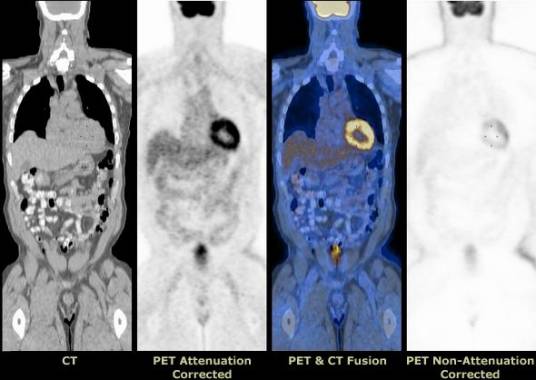

PET-CT将PET与CT融为一体,由PET提供病灶详尽的功能与代谢等分子信息,而CT提供病灶的精确解剖定位,一次显像可获得全身各方位的断层图像, 具有灵敏、准确、特异及定位精确等特点,可一目了然的了解全身整体状况,达到早期发现病灶和诊断疾病的目的。PET-CT的出现是医学影像学的又一次革命,受到了医学界的公认和广泛关注,堪称“现代医学高科技之冠”。

PET-CT是最高档PET扫描仪和先进螺旋CT设备功能的一体化融合,临床主要应用于肿瘤、脑和心脏等领域重大疾病的早期发现和诊断。